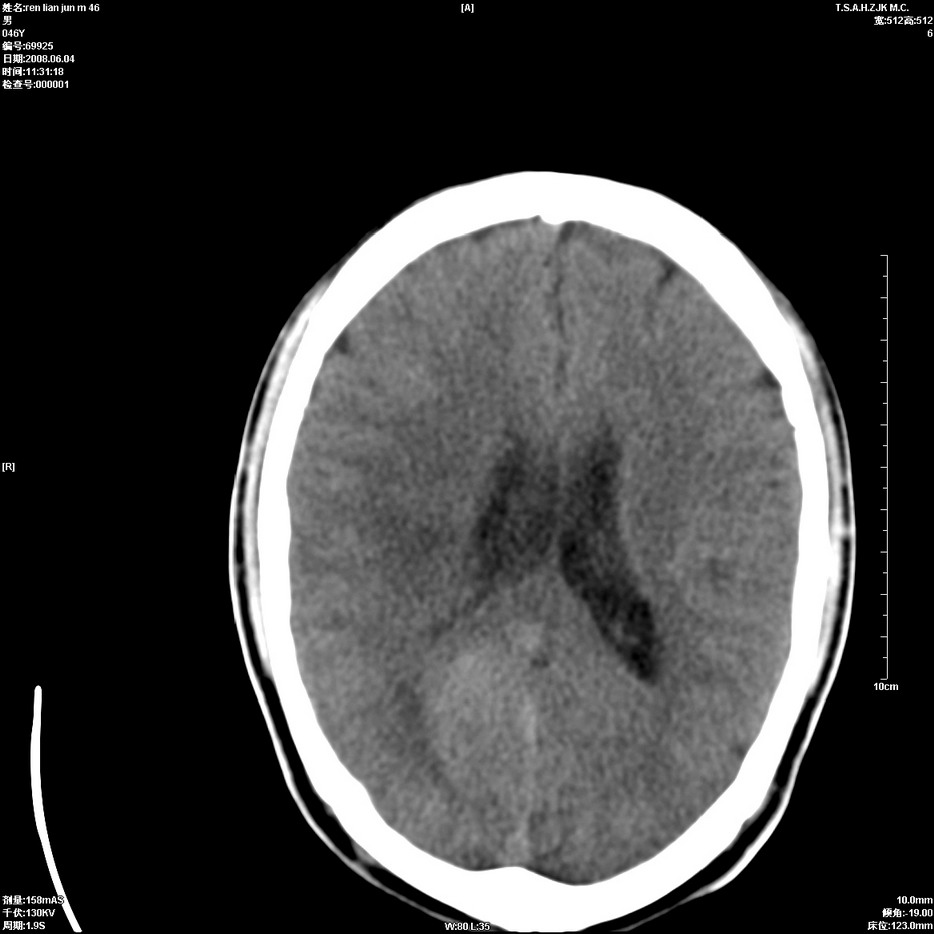

以下是引用qiu999在2008-6-5 17:14:00的发言:[br]考虑右肺中心型肺癌.颅内应做增强检查.

以下是引用形影不离在2008-6-5 19:18:00的发言:[br]右肺中心型肺癌并纵隔及左侧腋窝淋巴结转移,颅内应做增强检查。

以下是引用杀毒软件在2008-6-5 18:33:00的发言:[br]支持考虑右肺中心型肺癌,颅内病变是不是转移,不好说